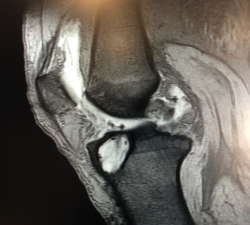

El tratamiento de un paciente que sufre una rotura aguda del LCA (Figura 2) sigue siendo motivo de discusión(9). Hay muchos condicionantes que influyen en el manejo terapéutico de estas lesiones (ya sea quirúrgico como no quirúrgico), como son la edad, la ocupación, la actividad deportiva, las lesiones asociadas, el grado de laxitud de la rodilla, las expectativas o las recidivas de la lesión, entre otras. El riesgo de artrosis tras la rotura aguda del LCA será mayor en ambos grupos con respecto a la población sana, sea cual sea el tratamiento(12). Los factores de riesgo más importantes para el desarrollo de artropatía son: lesión meniscal, meniscectomía e injerto hueso-tendón-hueso (HTH).

Figura 2. Rotura aguda del ligamento cruzado anterior.